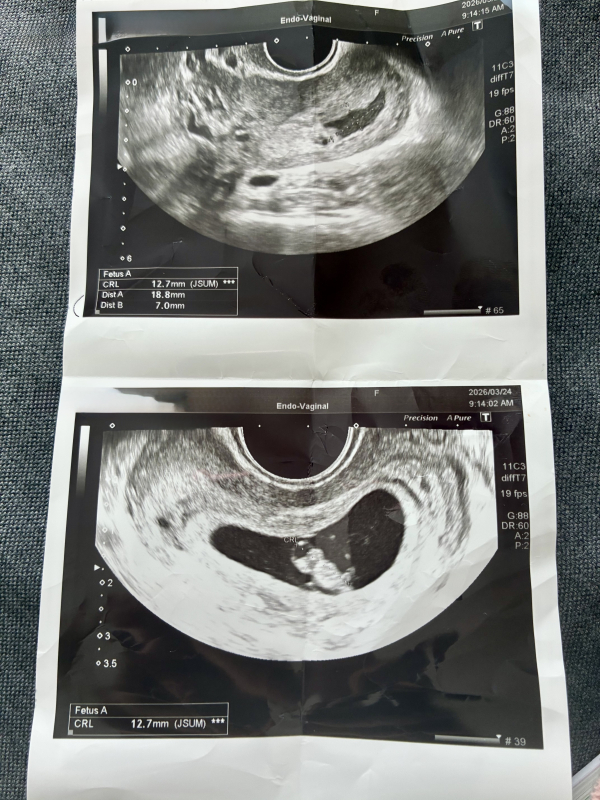

妊娠7週です。先日の健診で子宮内に出血があると言われました。赤ちゃんは順調に育っており、心拍確認もできました。特に安静制限も言われず薬も処方されず、1週間後に予定日と母子手帳の手続きするねといわれました。茶色の出血がでるかもしれないねと言われていますが、今のところ腹痛や出血なく経過しています。絨毛膜下血腫でしょうか?安静にとも言われていませんが、普通に生活していいのでしょうか?上が血腫で下が赤ちゃんです。

お写真からですと、絨毛膜下血腫なのかは、はっきりとは分かりませんが、子宮内に出血があると言われ、ご心配になりましたね。